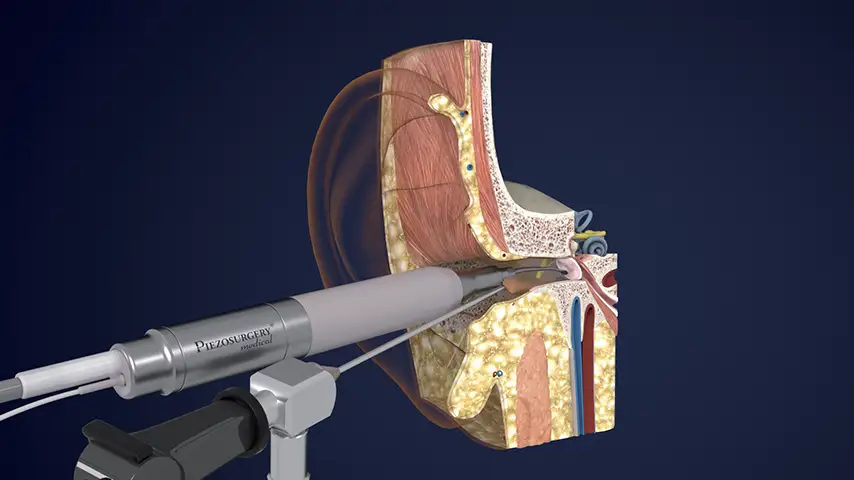

Cholesteatoma and middle ear pathologies

Selective osteotomies, safety on soft tissues

Advantages over traditional tools

Reduced risk of damaging anatomically complex regions

Greater intraoperative control and bone management

Micrometric cut for minimal bone loss

Reduced heat generation to avoid bone necrosis

CAVITATION EFFECT

Maximum intra-operative visibility.

Blood-free surgical site.